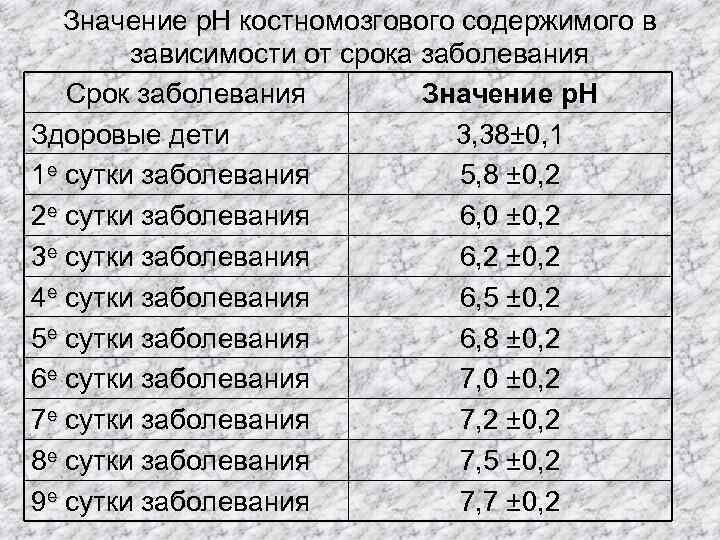

Значение р. Н костномозгового содержимого в зависимости от срока заболевания Срок заболевания Значение р. Н Здоровые дети 3, 38± 0, 1 1 е сутки заболевания 5, 8 ± 0, 2 2 е сутки заболевания 6, 0 ± 0, 2 3 е сутки заболевания 6, 2 ± 0, 2 4 е сутки заболевания 6, 5 ± 0, 2 5 е сутки заболевания 6, 8 ± 0, 2 6 е сутки заболевания 7, 0 ± 0, 2 7 е сутки заболевания 7, 2 ± 0, 2 8 е сутки заболевания 7, 5 ± 0, 2 9 е сутки заболевания 7, 7 ± 0, 2

Значение р. Н костномозгового содержимого в зависимости от срока заболевания Срок заболевания Значение р. Н Здоровые дети 3, 38± 0, 1 1 е сутки заболевания 5, 8 ± 0, 2 2 е сутки заболевания 6, 0 ± 0, 2 3 е сутки заболевания 6, 2 ± 0, 2 4 е сутки заболевания 6, 5 ± 0, 2 5 е сутки заболевания 6, 8 ± 0, 2 6 е сутки заболевания 7, 0 ± 0, 2 7 е сутки заболевания 7, 2 ± 0, 2 8 е сутки заболевания 7, 5 ± 0, 2 9 е сутки заболевания 7, 7 ± 0, 2